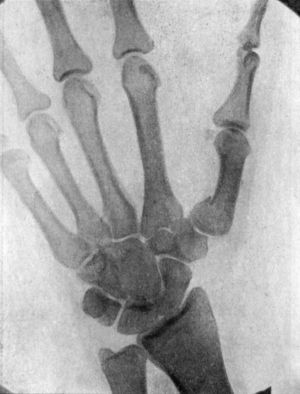

| 49. | Radiogram showing Fracture of Navicular (Scaphoid) Bone | 111 |

| 51. | Radiogram showing Forward Dislocation of Navicular Bone | 114 |